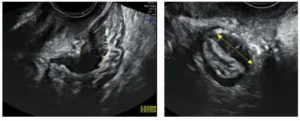

- La ecografía ginecológica realizada por manos expertas, que hoy en día se considera una técnica adecuada, precisa y suficiente para el diagnóstico en la mayoría de los casos, sin necesidad de recurrir a cirugía.